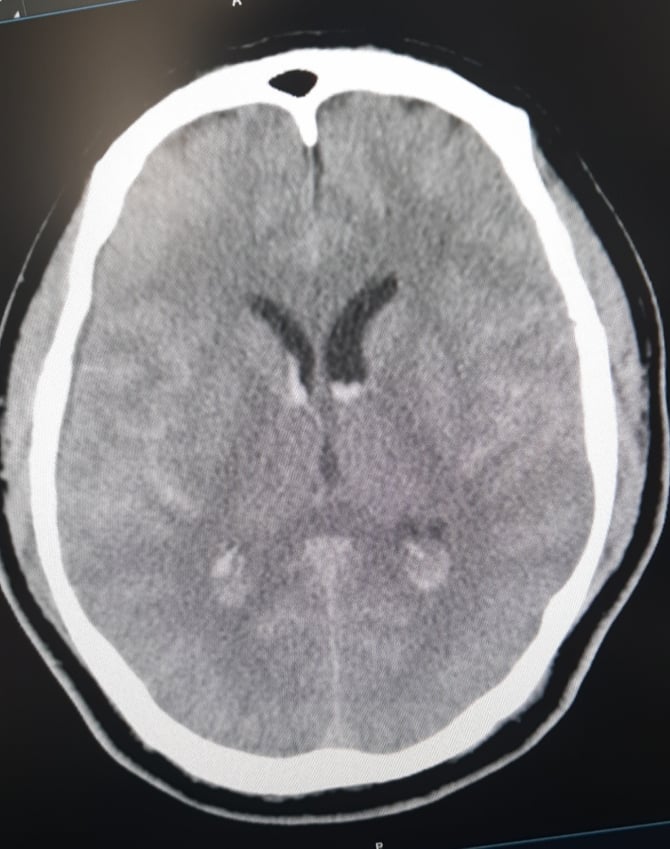

Hình ảnh Phim chụp xuất huyết dưới nhện lan tỏa – tụ máu não thất

Ngay khi tiếp nhận, các bác sĩ Trung tâm Đột quỵ đã nghi ngờ nguyên nhân chảy máu dưới nhện là do dị dạng mạch não. Bệnh nhân được đi chụp CTA – chụp mạch não phát hiện: chảy máu dưới nhện lan tỏa – chảy máu não thất do vỡ phình lóc tách động mạch đốt sống phải đoạn V4. Đây là một tổn thương có vị trí khó, phức tạp và tinh vi, thường cần một bác sĩ chẩn đoán hình ảnh chuyên sâu và nhiều kinh nghiệm mới chẩn đoán được.